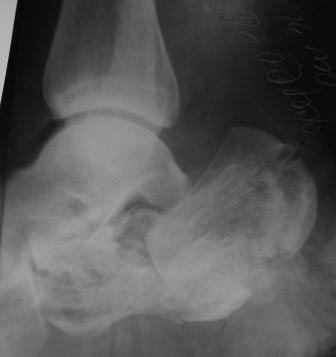

Вчера госпитализирован пациент 1970г.р., в ноябре 2014г, получил

о/перелом пяточной кости. в другой клинике произведена КДО аппаратом

Илизарова, после трех месяцев аппарат сняли, и больной начал наступать и

ходить, все это со слов больного (р-снимков нет.). Жалобы боль при

ходьбе, которая в динамике усиливается, об-но: деформация пяточной

кости, движение в г/стопном суставе почти в полном объеме, по медиальной

поверхности пятки рубец, плотно спаянный с костью.

Предварительный план: корригируюшая остеотомия пяточной кости, для

создания свода стопы (сможем ли опустить бугор пяточной кости из-за

натяжения ахиллово сухожилия), и подтаранный артродез.